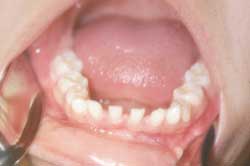

Tejidos duros: Ausencia clínica de los siguientes dientes: 12, 13, 14, 15, 17, 23, 24, 25, 27, 31, 32, 33, 34, 35, 37, 41, 42, 43, 44, 45, 47 los cuales deberían encontrarse presente según la edad dental y cronológica del paciente. Fig. 2 y 3

Figura 2 Aspecto intrabucal

Figura 2

Aspecto intrabucal

Figura 3 Aspecto intrabucal

Figura 3

La paciente no presentó desviaciones mandibulares en apertura y cierre, no hubo ruidos ni chasquidos audibles. Se observaron espaciamientos en las zonas antero superior y antero inferior.